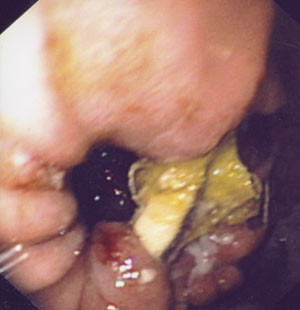

Pasienten ble utskrevet fra sykehuset i god allmenntilstand samme dag som den første gastroskopien ble utført. To dager senere gjennomførte vi ny gastroskopi. Med den kirurgiske saksen klippet vi over båndet (fig 2). Prosedyren tok ca. en halv time, da båndet var temmelig hardt og kjeften på saksen nokså liten. Etter at båndet var klippet over, ble en slynge ført gjennom endoskopet. Med den fattet vi tak i den ene enden av båndet (fig 3). Hele båndet ble trukket ut uten vesentlig motstand og fjernet aboralt (fig 4). Det tilkom ingen umiddelbare komplikasjoner. Prosedyren ble utført poliklinisk, men pasienten ble observert tre timer etterpå.